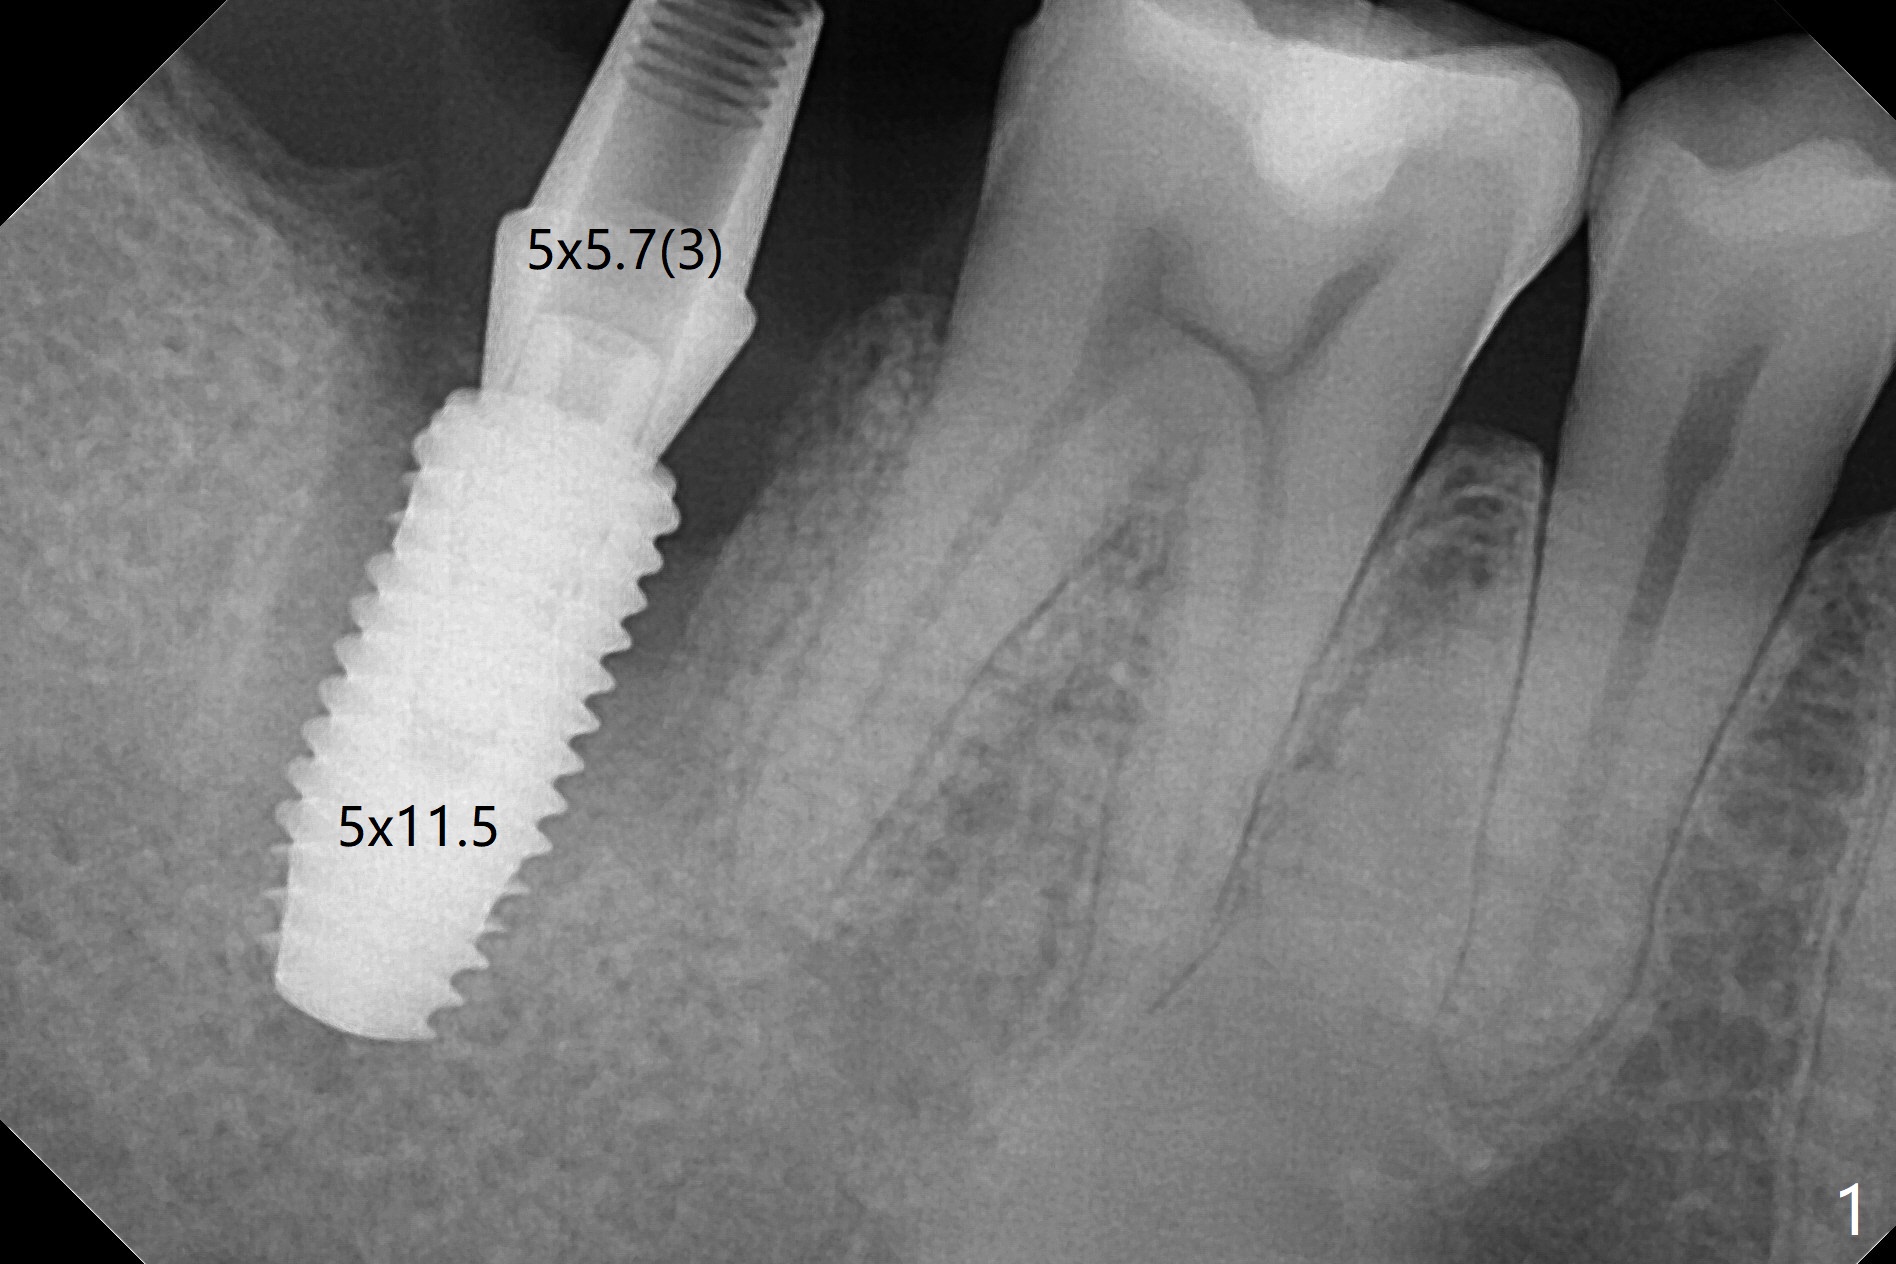

右下七5x11.5毫米植体导板植入根尖骨质大约2-3毫米(图一),扭力~50 Ncm,即使发生骨坏死,不会产生植体周围炎,最坏植体松动脱落。放置基台后,植入大量粘性骨粉(图二:*),覆盖PRF(图三);如果使用临时牙冠关闭牙槽窝,牙冠与龈缘(箭头)接触不紧,使用水牙线冲洗,骨粉流失严重。所以采纳树脂敷料(图四:A),后者边缘至少覆盖牙槽窝口1-2毫米,一周复查,及时关闭术后牙龈退缩所造成的漏洞。其实病人术后第二天回来,敷料脱落,理由:远中无牙,基台短(图五)。Return to Prevent Molar Periimplantitis (Protocols, Table) Protect Graft Torque 第一磨牙即种 Xin Wei, DDS, PhD, MS 1st edition 04/27/2021, last revision 04/29/2021